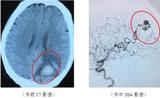

近日,64岁的顾大爷因头痛不适来我院检查,头颅CT显示:左侧顶枕叶脑出血。了解既往无明确高血压病史,收住院后因神志清晰且脑出血量小故予以补液、止血、支持等保守对症治疗,病情逐渐稳定,分析出血原因考虑:患者既往无明确高血压病史且病程中亦无明显高血压症象;脑出血部位为非高血压引起的基底节区;&...2017-08-22